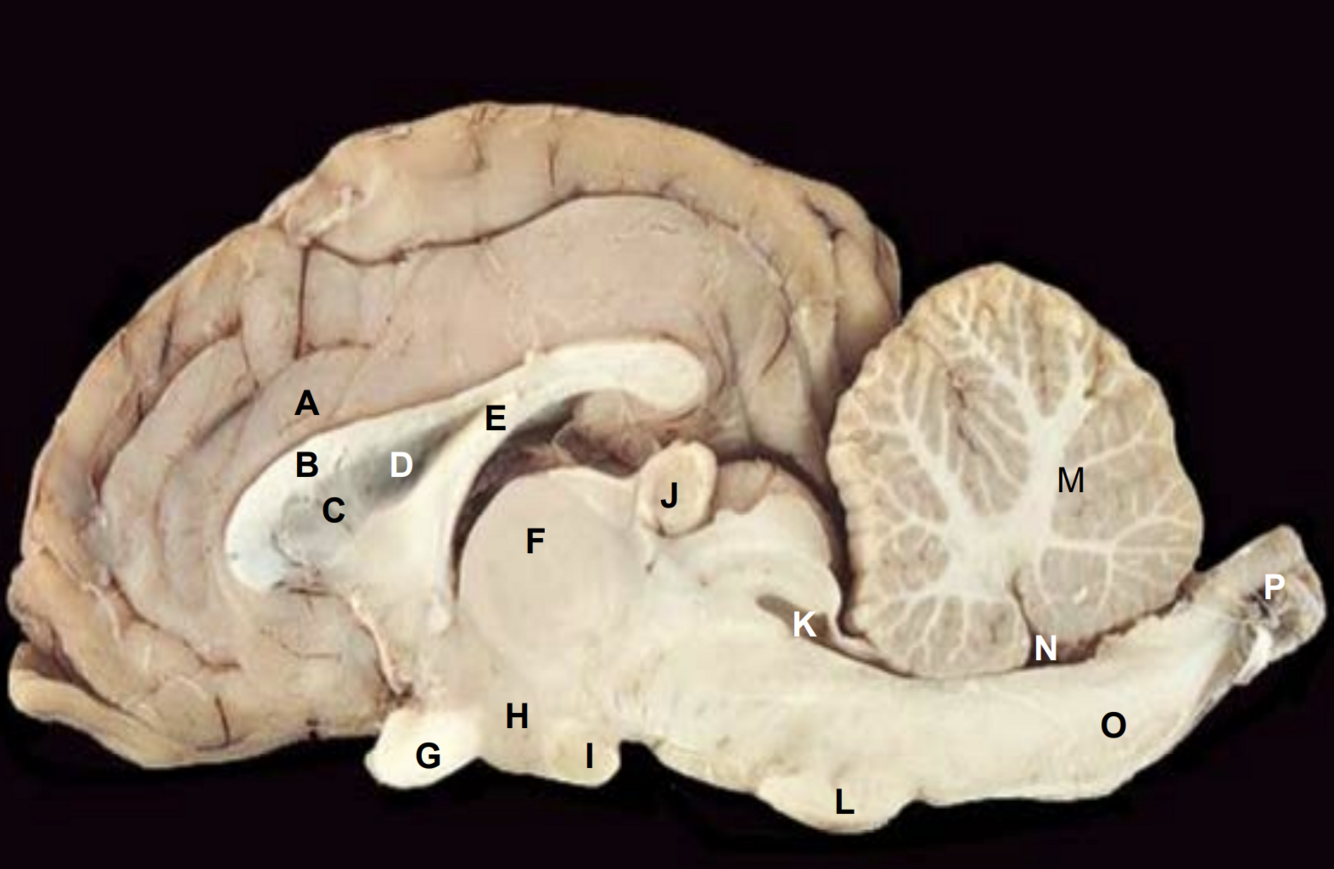

Cingulate gyrus

Corpus callosum

Septum pellucidum

Lateral ventricle

Fornix

Thalamus

Optic chiasm

Hypothalamus

Mammillary body

Pineal gland

Cerebral aqueduct

Pons

Arbor vitae

4th Ventricle

Medulla